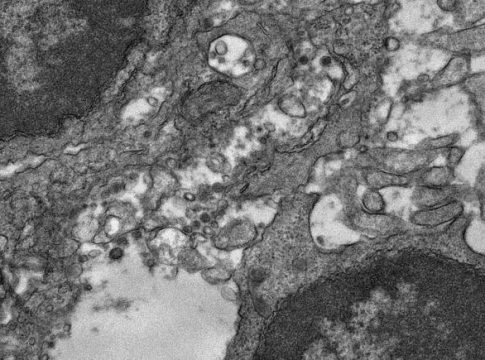

Estudios publicados anteriormente mostraron que los pacientes que necesitan tratamiento hospitalario debido a la COVID-19 recién diagnosticada tienen un metabolismo de la glucosa reducido en el cerebro, lo que se asocia con el deterioro de la función cognitiva. Para evaluar si los pacientes que sufren COVID de larga duración experimentan déficits similares, los investigadores realizaron pruebas neuropsicológicas e imágenes PET de 18F-FDG cerebrales.

Se recomendó la realización de imágenes PET con 18F-FDG a todos los pacientes que recibieron asesoramiento, y 14 de los 31 pacientes procedieron a ello. La evaluación clínica del escáner de cada paciente no reveló hallazgos patológicos distintos ni diagnósticos alternativos. Cuando se compararon las exploraciones con las de un grupo de control, no se observaron diferencias significativas.